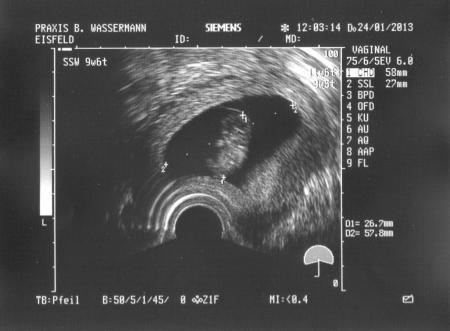

und hier noch von der 9 ssw. um das mal nachzureichen find das bild soooooo knuffig war das erste mal als ich mein krümmel sehen konnte

Bild zu